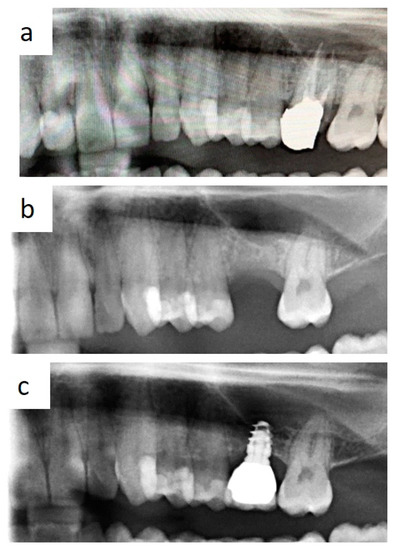

Bone loss around implant was measured at the time of second surgery (three months later) with healing cup positioning (values ranging from 0 to 0.6 mm; median value: 0.1 mm) and also after two years (values ranging from 0.4 to 1.3 mm; median value: 0.7 mm). Clinical post-operative complications did not occur. (Figure 6a–e and Figure 7a,b) To date, no implant failure has occurred during the ten-year follow-up, as summarized in Table 1.

Figure 6. Intraoperative view of implant insertion by muco-periosteal flap elevation (a,b); the implant diameter is larger than implant site preparation, thus promoting bone dislocation in the apical direction by the self-tapping capability of the fixture and high primary stability. Radiological follow-up 3 months after insertion (c), 2 years after prosthetic rehabilitation (d), and after 10 years (e).

Figure 7. Periapical radiograms showing the bone loss at a 2-year (a) and a 10-year follow-up (b) around a short spiral implant (6.25 × 4.2 mm in diameter) supporting a single metal–ceramic crown.